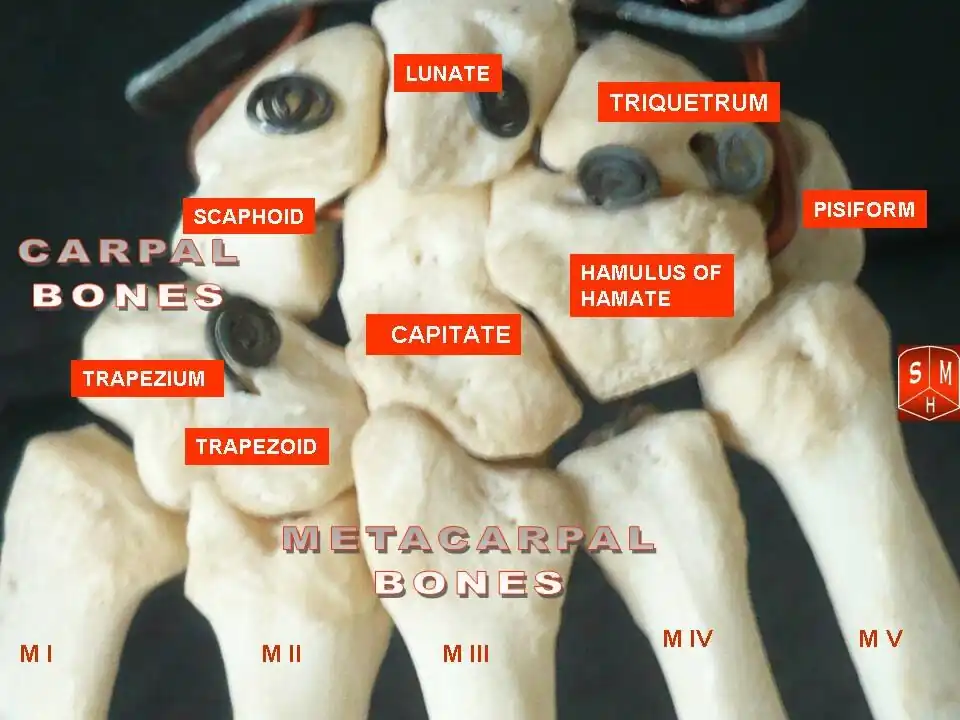

Besides the metacarpophalangeal joints, the metacarpal bones articulate by carpometacarpal joints as follows:

- the first with the trapezium;

- the second with the trapezium, trapezoid, capitate and third metacarpal;

- the third with the capitate and second and fourth metacarpals;

- the fourth with the capitate, hamate, and third and fifth metacarpals;

- and the fifth with the hamate and fourth metacarpal;

Carpometacarpal joints of the left hand. Thumb on left.

Carpometacarpal joints of the left hand. Thumb on left. -

Carpometacarpal joints of the left hand. Thumb on left.

Carpometacarpal joints of the left hand. Thumb on left. -